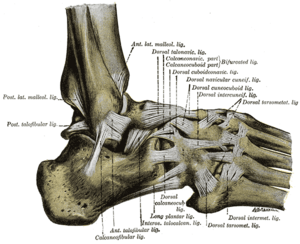

The ligaments of the foot from the lateral aspect. (Calcaneocuboid labeled at top, third from right.) | |

Ligaments

The ligaments connecting the calcaneus with the cuboid are five in number, viz., the articular capsule:

- the dorsal calcaneocuboid ligament,

- part of the bifurcated ligament,

- the long plantar ligament,

- and the plantar calcaneocuboid ligament.